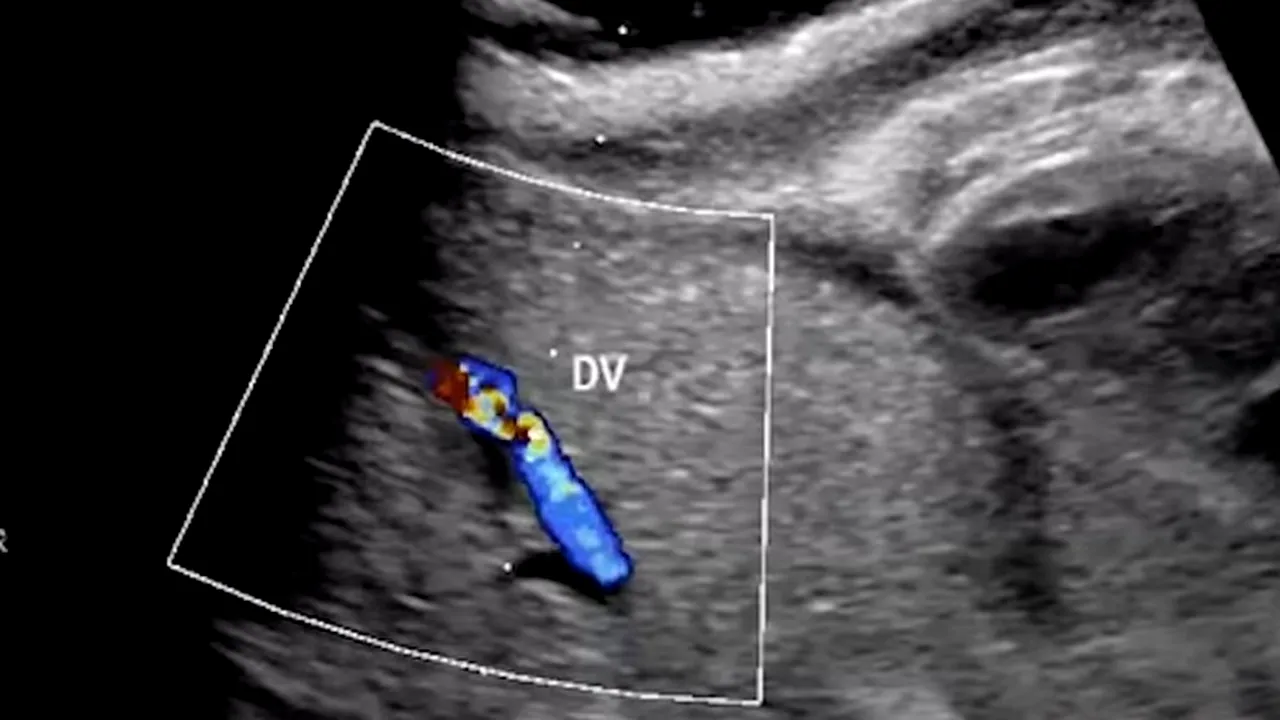

În interiorul acestui dispozitiv inima prematurului pompează singură sângele prin intermediul cordonului ombilicat conectat la o mașinărie care asigură schimbul de gaze, ținând locul placentei mamei, în timp ce lichidul amniotic articial îmbogățit cu nutrienți asigură dezvoltarea fătului, intrând și ieșind din punga sterilă în care stă acesta din urmă.